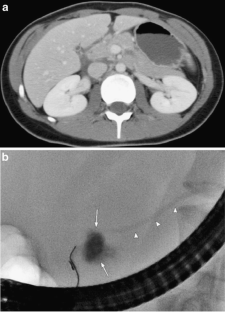

Fig. 2